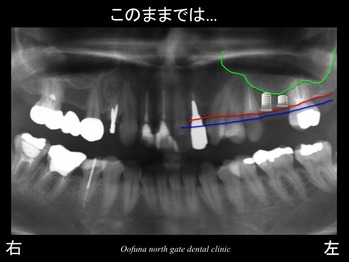

上顎左側の奥歯が2歯分が欠損していました。

上の写真の青線は、本来(もともと)の骨の位置を表しています。

赤線は、現在の骨の位置です。

簡単に言えば、青線から赤線まで骨が吸収したのです。

話は、レントゲン緑線になります。

緑線は、上顎洞です。

上顎洞は、空洞なのです。

骨ではなく、穴が開いているのです。

そのため、現在骨の高さは、非常に少ないのです。

もし、このままの状態でインプラントを埋め込もうとすると

以下のような短いインプラントしか埋め込むことができなくなります。

これでは、インプラントの将来性は低いと言えます。